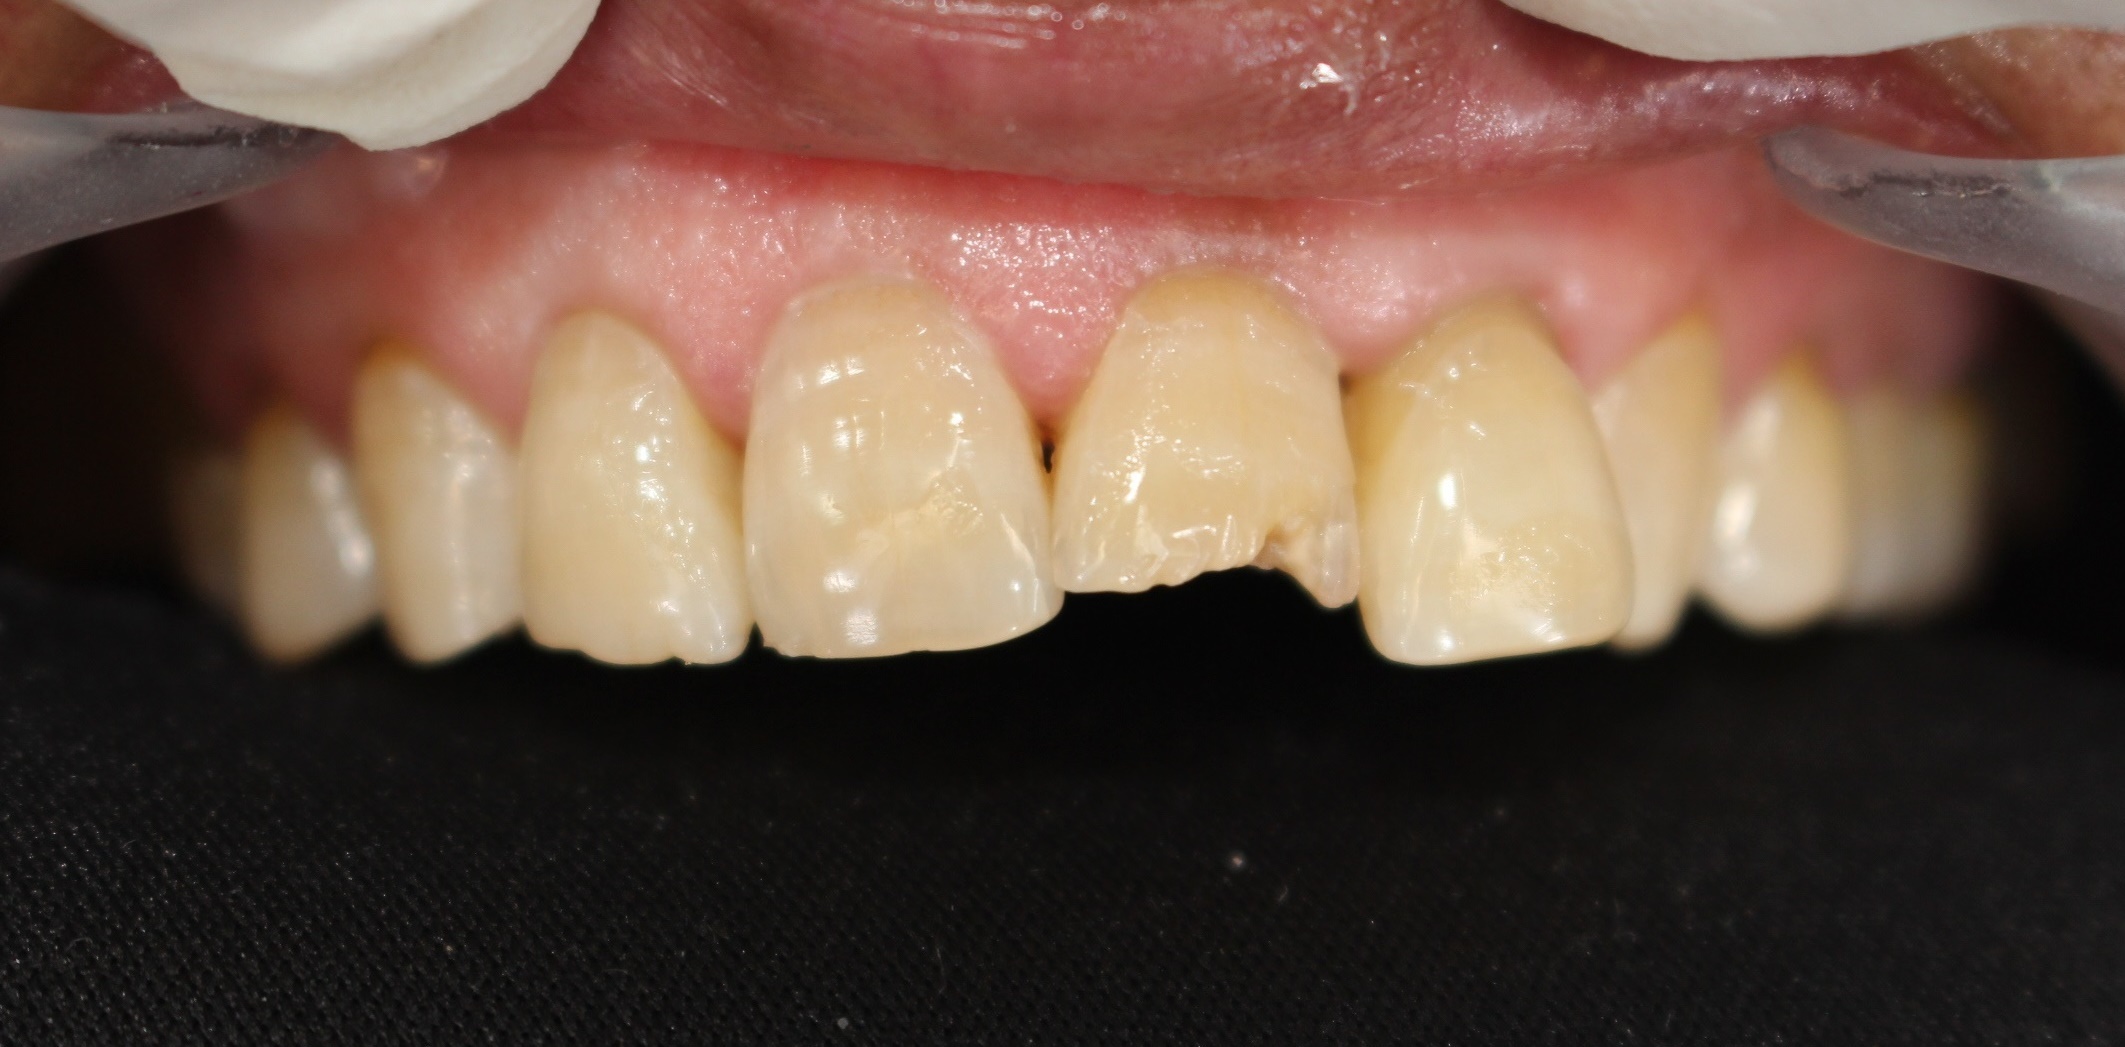

전치부절단면레진

전후사진